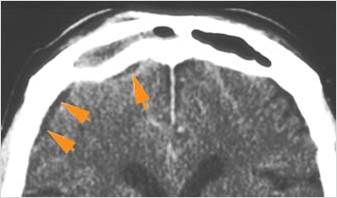

74-year old insulin-dependent diabetic female in the emergency room with fever, sinusitis with possible orbital, intracranial or other complications such as cavernous sinus thrombosis.Exam

Findings are consistent with the clinical diagnosis of acute or subacute ethmoid and most importantly sphenoid sinusitis, possibly fungal, with left superior ophthalmic vein thrombosis, early tension orbit and cavernous sinus thrombosis.